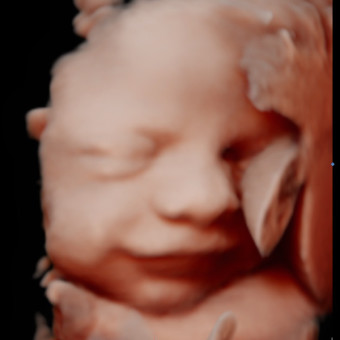

Baby Boy Bowker

Sydney Bowker

Vero Beach, FL

January 2, 2026